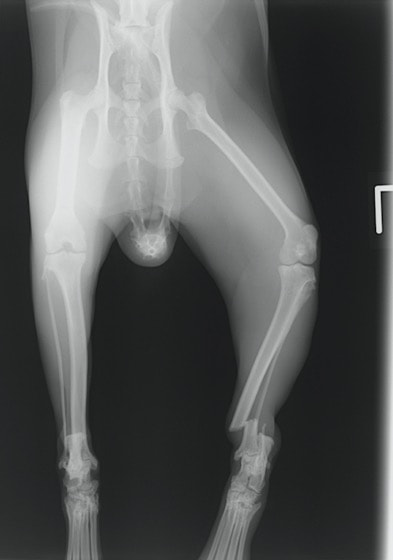

症例3:キルシュナーワイヤーのピンニングによる整復

ペルシャ猫 11ヶ月齢 雄

他院にて左大腿骨遠位の成長板骨折(salter-harrisⅠ型)が認められており、治療相談を目的として来院。当院にて、キルシュナーワイヤーを用いたピンニングにより骨折部位の整復を行いました。術後の経過は良好で、現在も経過観察中です。

術前レントゲン

術後レントゲン